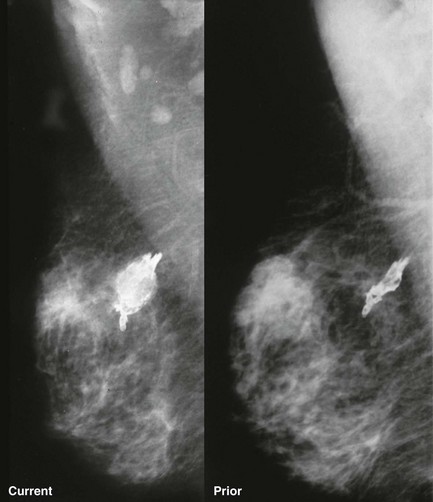

Osteosarcoma presents as a really strange looking calcification almost anywhere in the body (Fig. 11-16). The primary and metastatic lesions may show increased activity on bone scintigraphy.

FIGURE 11-16 Osteosarcoma of the Breast.

The calcification appears lucent-centered, although not typical for dystrophic calcification. It increased in size and became palpable since the mammogram from 6 months earlier. (Reprinted from Harvey JA, Fondreist JT, Smith MM. Densely calcified breast mass. Invest Radiol 1994;29:516-517.)